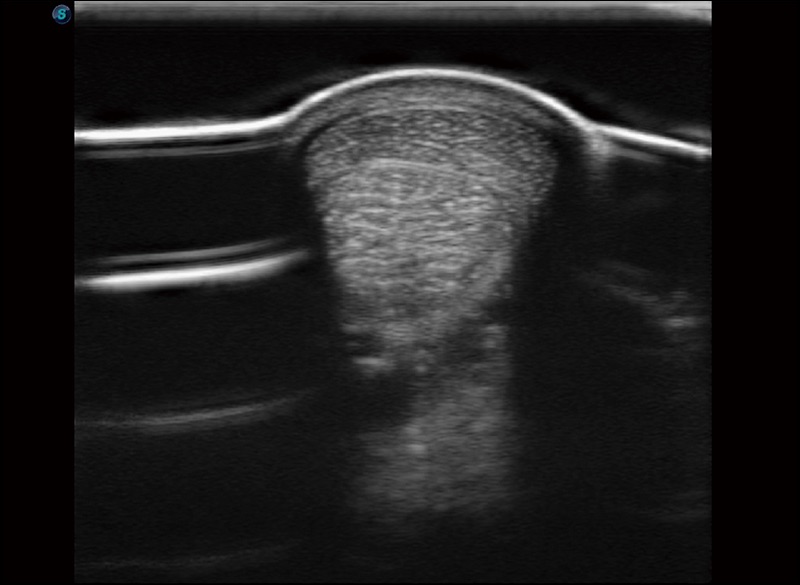

临床图